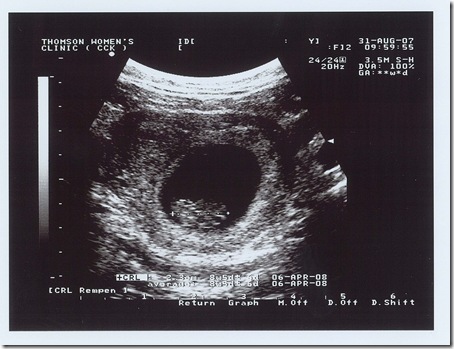

31/Aug/2007

scan_20070831